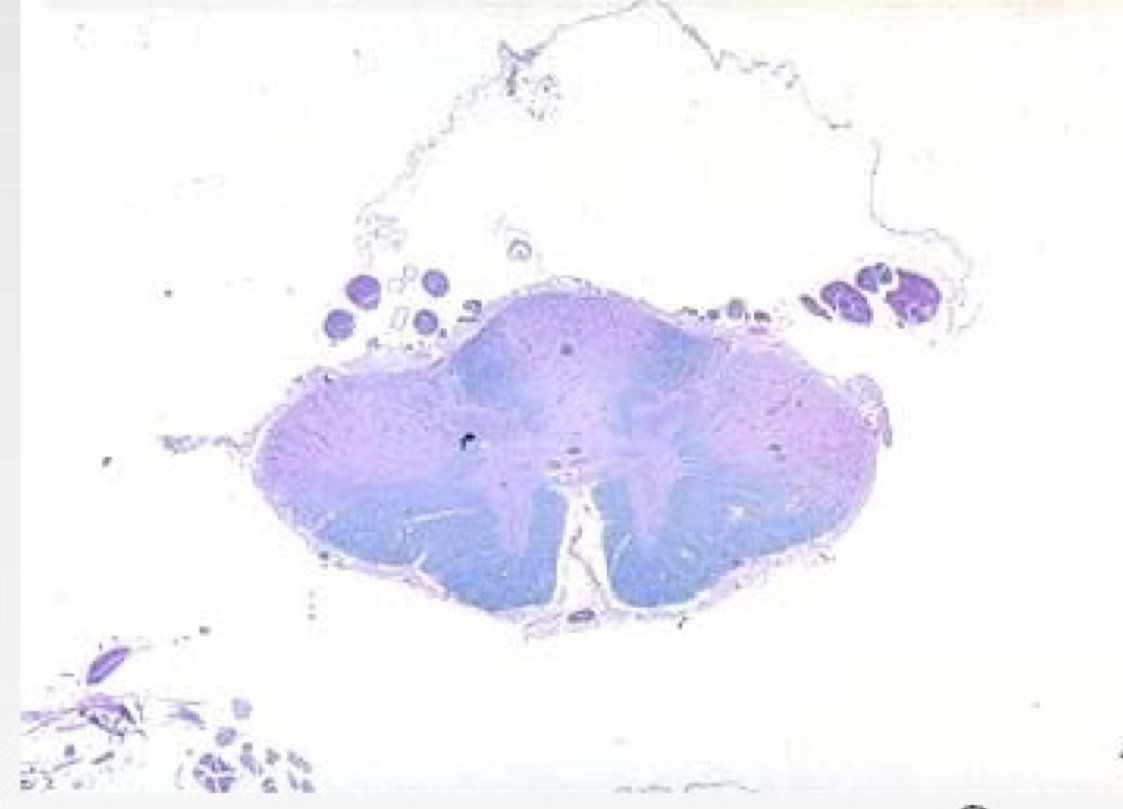

What is this?

B12 or HIV

Subacute combined degereration of the cord